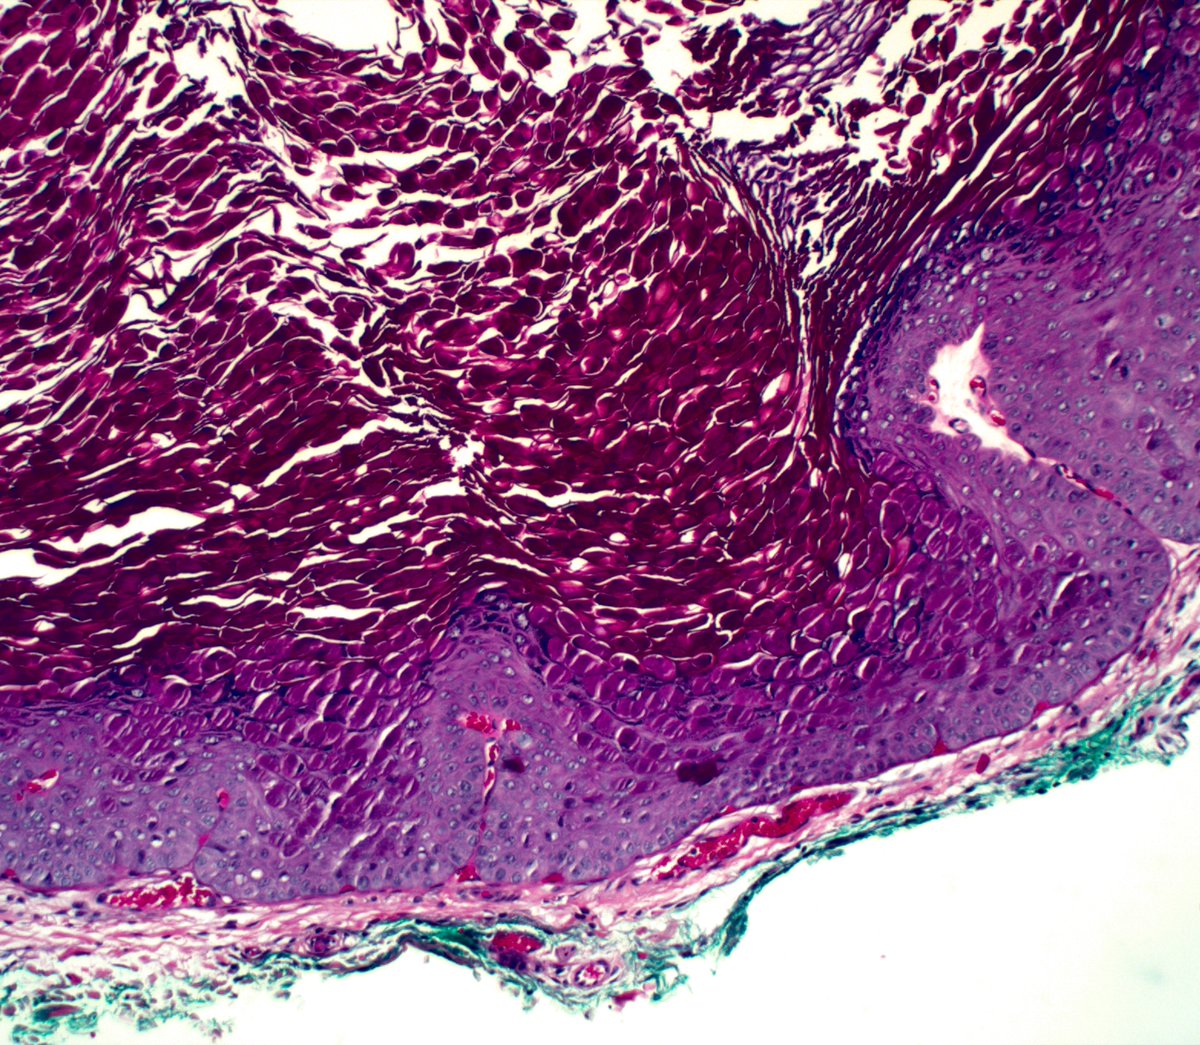

🔬Molluscum contagiosum.

👤72F. Chest.

Textbooks say it is a childhood disease or passed sexually. Anecdotally, any body can get it anywhere at any age.

#dermpath #dermatology #dermtwitter #pathology